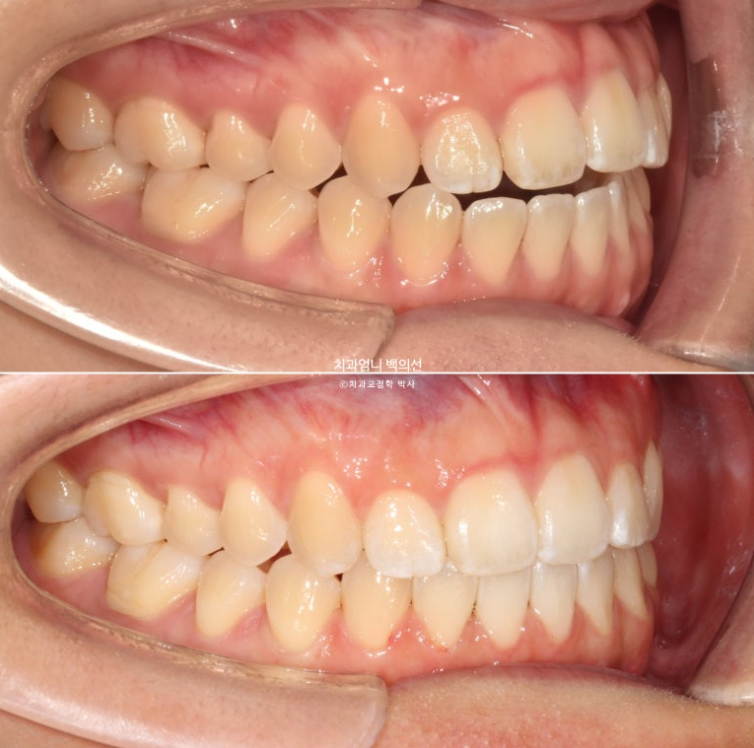

사용한 부분교정용 장치는 MTA 미니튜브 이고 고무줄 처방이 함께 들어갔습니다.

윗니가 아랫니를 앞에서 안정적으로 덮게 만들려면 아래 앞니에 치간삭제가 소량 필요합니다.

24년 12월부터 25년 6월까지 걸린기간은 총 6개월 입니다.

25.06

24.12~25.06

원래 좋았던 교합은 잘 유지가 되었습니다.